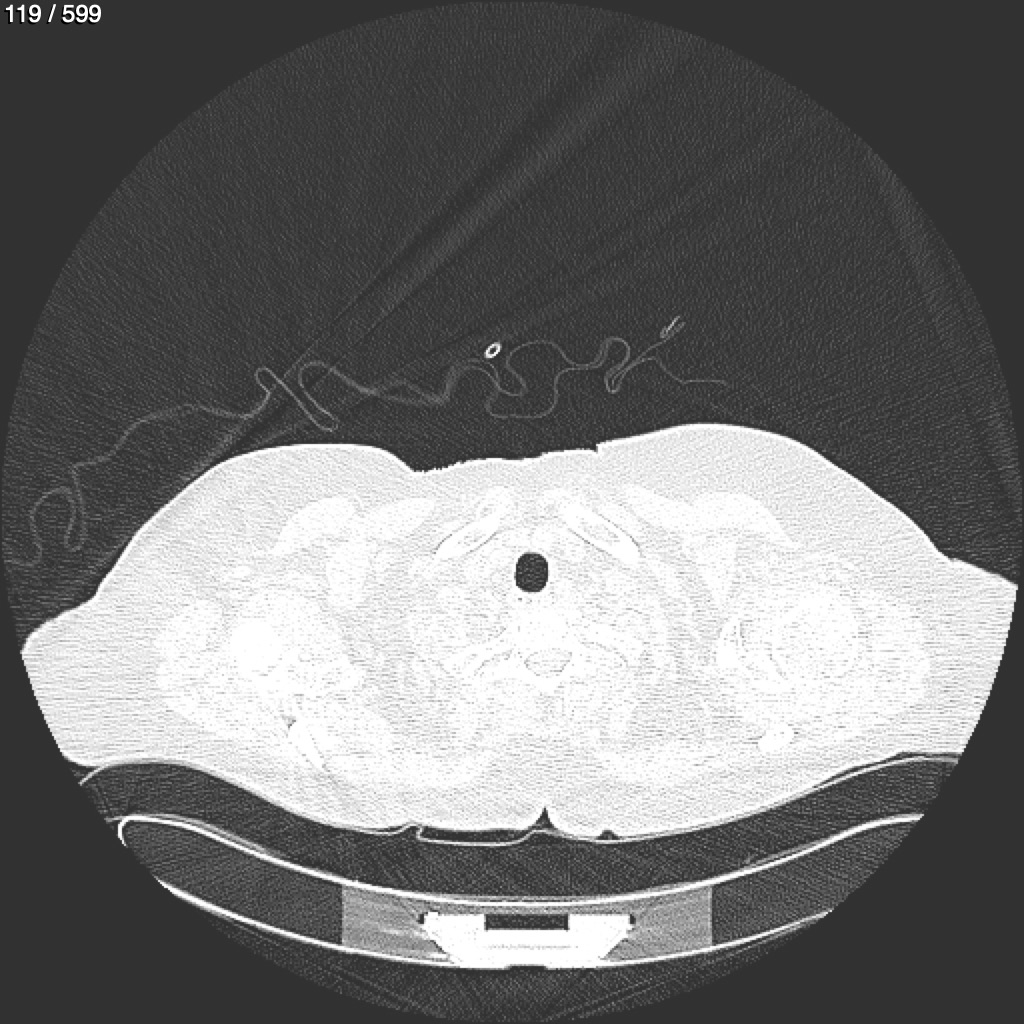

Home G​l​o​r​i​a​ ​G​l​a​d​y​s​ ​B​e​a​s​l​e​y​ ​-​ ​T​ó​r​a​x​ ​T​o​r​a​x​_​S​i​m​p​l​e​ ​(​A​d​u​l​t​o​)